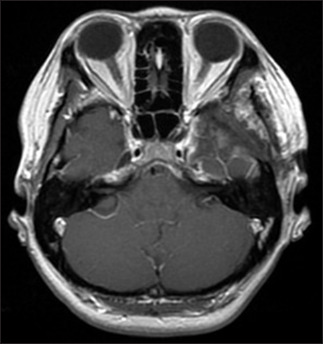

Case description: A case of a 42-year-old woman presented with facial numbness and headache. Magnetic resonance imaging revealed a 25-mm enhancing mass in the left Meckel cave, initially suspected to be a trigeminal schwannoma. Craniotomy and tumor resection were performed. Intraoperative findings and rapid pathology indicated marked inflammatory cell infiltration without features of schwannoma. The final diagnosis was inflammatory pseudotumor, with no evidence of IgG4-related disease or malignancy. Postoperative symptoms improved, and only a short course of steroids was administered.